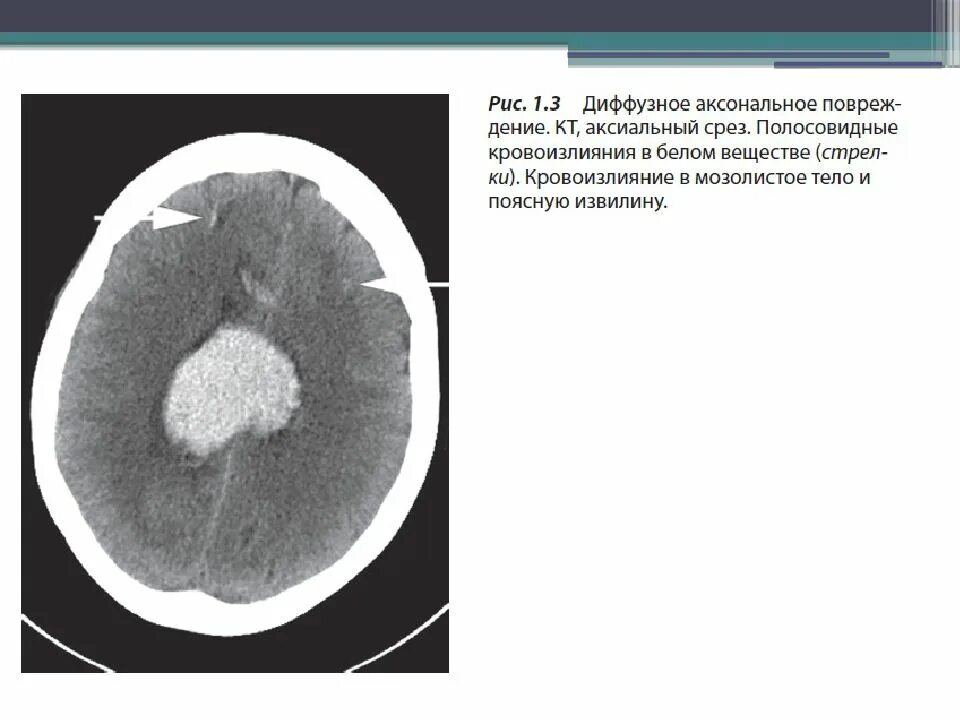

Диффузное аксональное повреждение